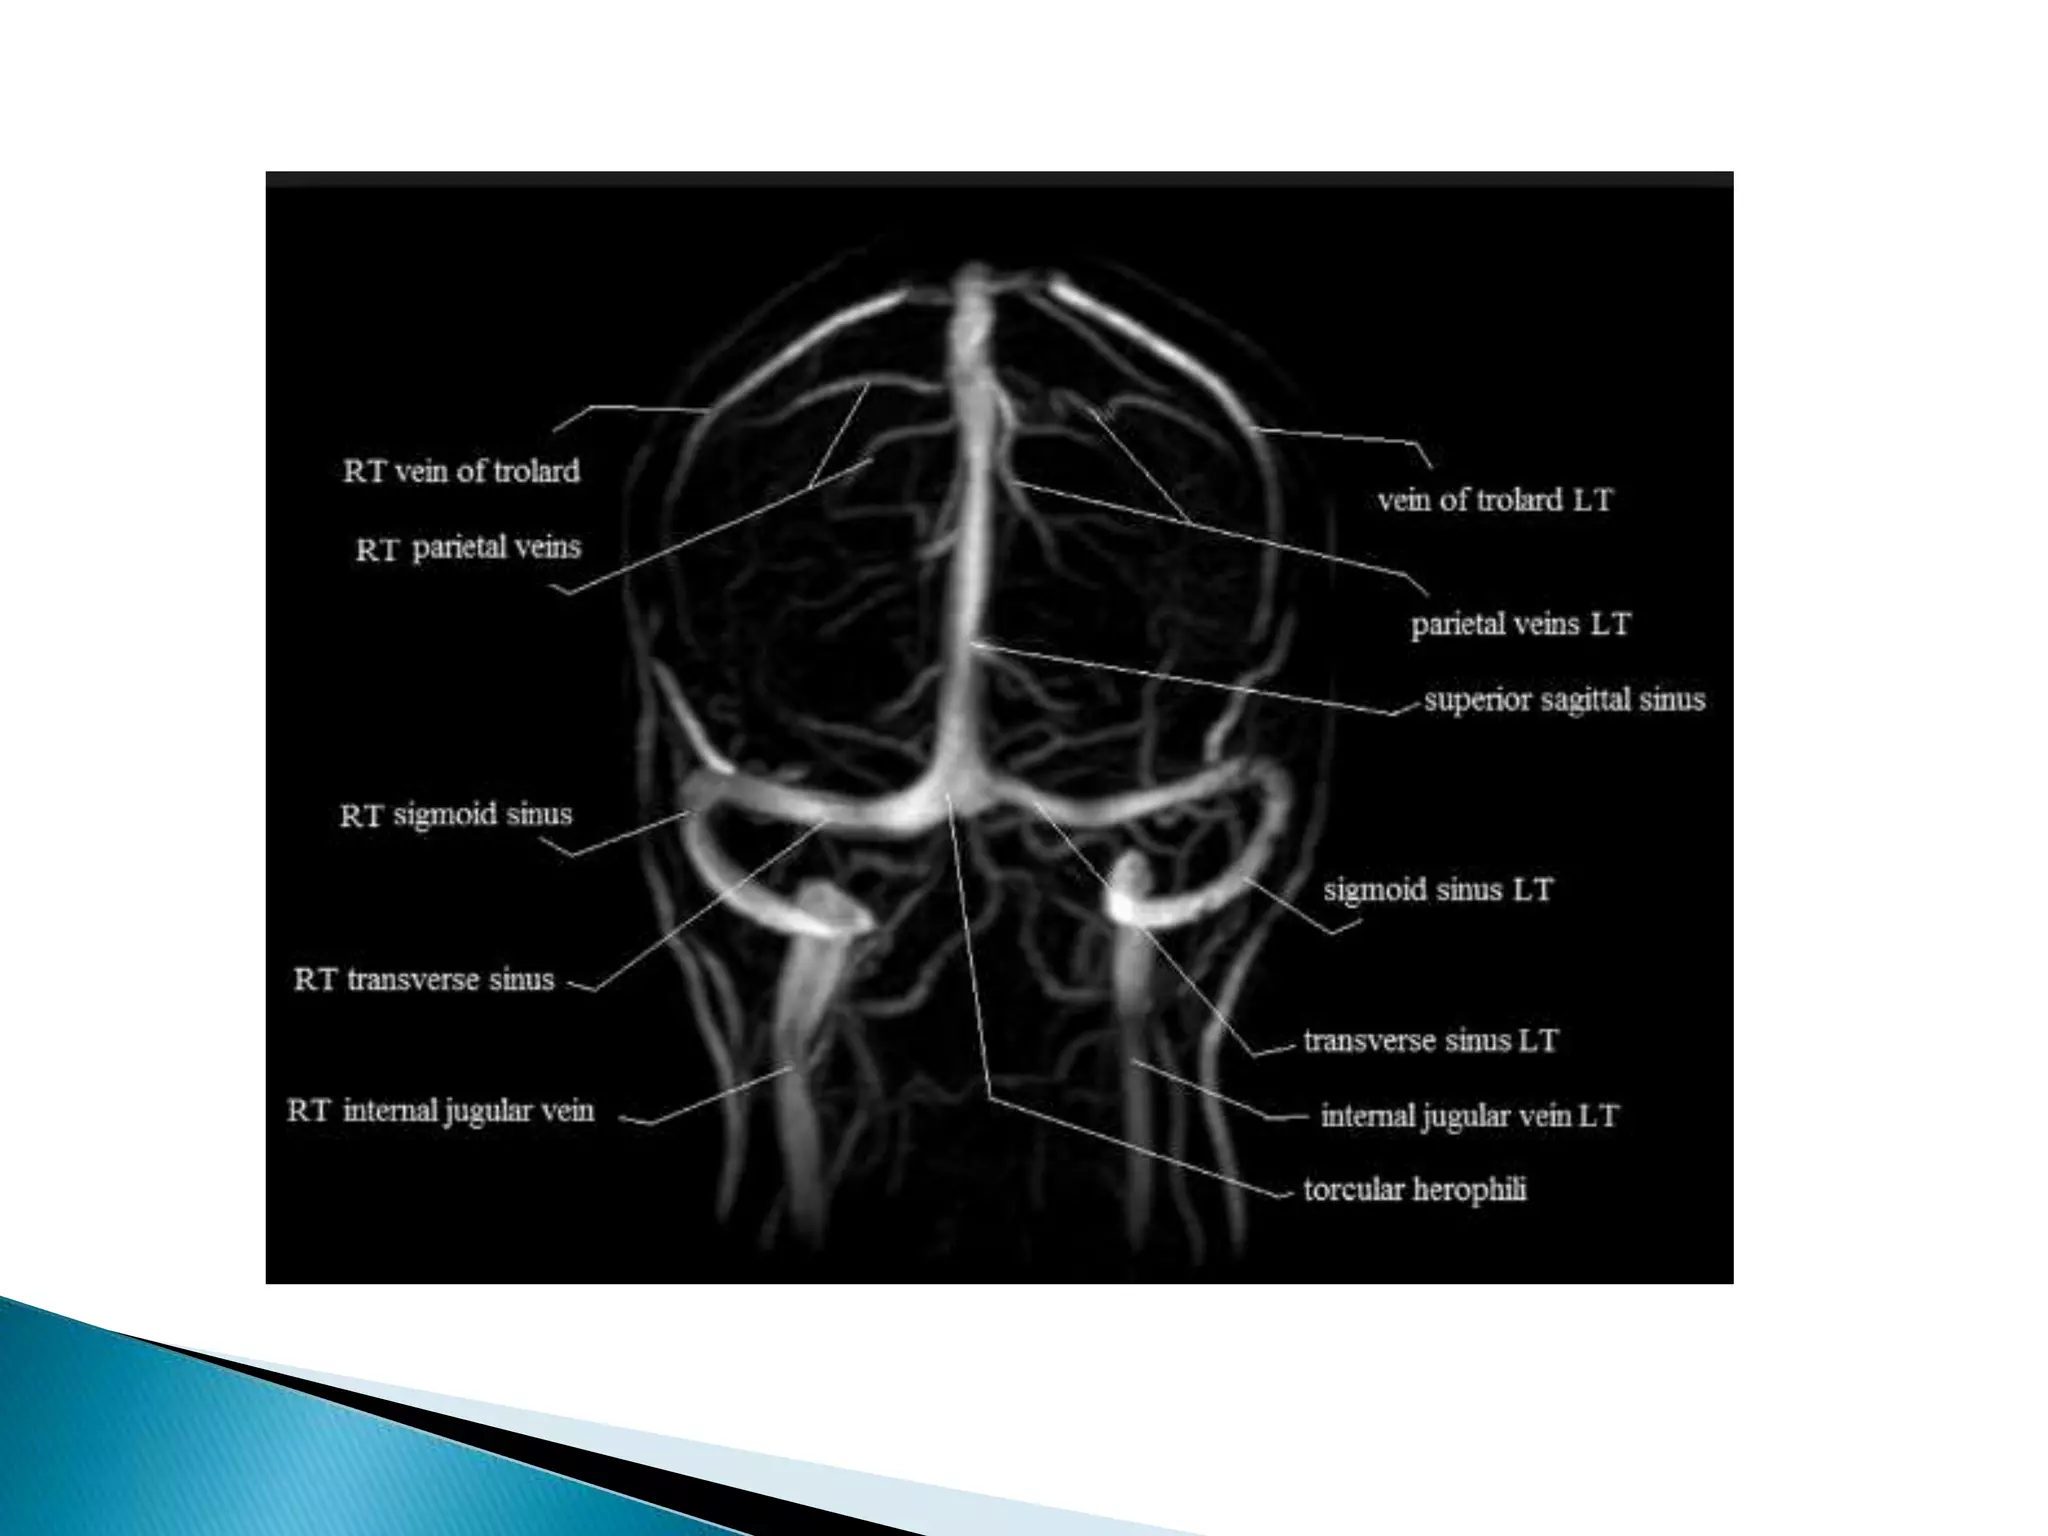

This document lists various medical conditions and provides brief descriptions: A) Abscess, B) Brain infarction and hypoxic insult, C) Crutzfield Jacob disease, D) Diffuse axonal injury and demyelination, E) Encephalitis caused by HSV virus and epidermoid cyst. It also mentions imaging sequences and differential diagnoses for conditions like ischemic stroke and limbic encephalitis.